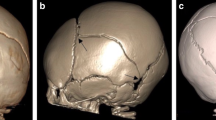

The objective of the FE simulations of the 11 cases was to reproduce both the impact force-time history (Fig. 2) captured in the fall reconstructions as well as the head impact location and orientation as described in witness and radiology reports (Fig. 3). To consider the possible range of head impact forces that might have been applied during each fall, 3 trials (reproducing the first (Q1), second (Q2), and third (Q3) quartile of the measured force-time histories in the reconstruction drops) of each of the 11 cases were simulated (N = 33) in ABAQUS explicit. For each FE simulation, the initial velocity of the head was adjusted until the simulated impact force-time history matched the peak and duration of experimental impact force trace within 5% error tolerance (Fig. 2, Table 4). For the seven cases with skull fracture, the distribution of stress and strain in the FE model was compared to the skull fracture location to confirm that high values occurred in the elements located around the site marked as fracture by the neuroradiologist. For some cases, the head orientation and impact location were adjusted slightly, still consistent with the witness reports and videos of reconstruction drops, and the simulation was re-run. As bilateral parietal fractures have been reported in both clinical [36] and cadaveric studies [15, 16], the results of both right and left parietal plates were used in this study. For each simulation, peak temporal values of four fracture predictors (first principal stress, first principal strain, maximum shear stress, and von Mises stress) were extracted from every element in the right and left parietal skull plates.

The distribution of the first principal stress and strain, and von Mises stress, along with the clinical location of fracture, for the seven cases with fracture are shown in Fig. 4. The first, second, and third peak head impact force quartiles (Q1-Q2-Q3) measured in the reconstruction experiments and obtained from the corresponding simulations for all 11 cases are summarized in Table 4. The peak impact forces from the FE simulations are all within 5% error tolerance of the experimental values, indicating that the reconstructed FE simulations are well matched to the surrogate reconstructions.

For each potential skull fracture predictor, 66 data points were extracted from the FE simulations (3 simulations per case, 11 cases, 1 maximum data point per simulation from each of 2 parietal skull plates). Each data point was assigned a designation of presence of parietal fracture or absence and is displayed in Fig. S1. The parietal skull fracture risk curves derived from binary logistic regression analysis (Fig. 5) for the four predictor candidates show the least overlap in values for fracture and no fracture for maximal principal stress and strain. Quantitative analysis of the risk curve prediction accuracy for each of the four predictor candidates, evaluated by the AUROC, prediction accuracy rate, the Nagelkerke R2, and the Cox and Snell R2 statistics (Table 6), confirm that the best predictors were first principal stress and first principal strain. These predictors had the highest statistical correlations with AUROC (0.933), prediction accuracy rate (90.9 and 86.4%), Nagelkerke R2 (0.727 and 0.723), and Cox and Snell R2 (0.519 and 0.516). The threshold values corresponding to the 50 and 95% probabilities of parietal skull fracture, as determined from the developed injury risk curves for the four predictors are provided in Table 7. Injury threshold values from the ROC analysis demonstrate close agreement with the 50% fracture risk threshold values determined from binary logistic regression curves (Table 7). For each of the four skull fracture predictor candidates, Q1, Q2, and Q3 curves (Fig. 5) demonstrated very similar trends and statistical results (Table 6). Threshold values (Table 7) obtained from these curves are also consistent.